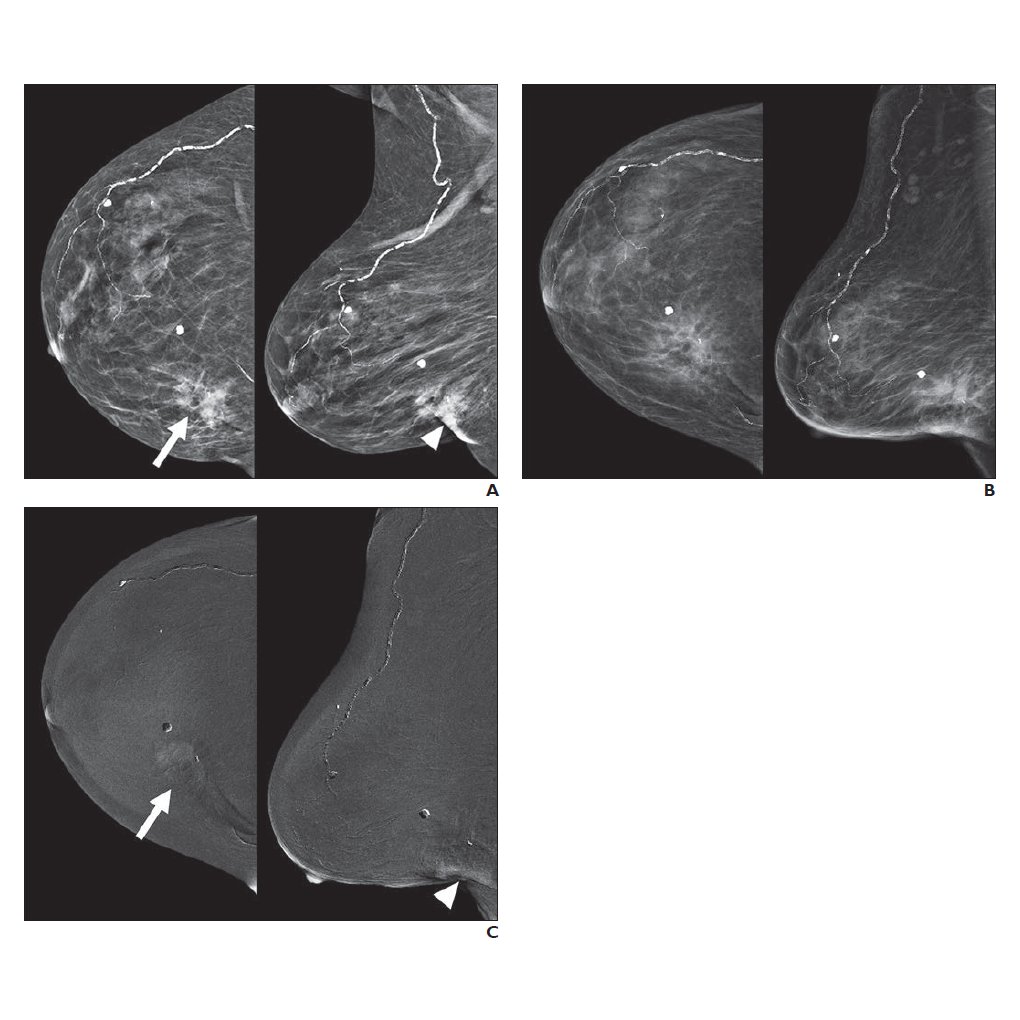

CEM may be used for follow-up imaging of patients after breast cancer cryoablation, having several advantages for this purpose compared with alternate imaging modalities.ajronline.org/doi/10.2214/AJ…